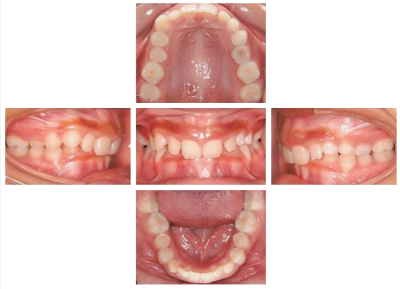

13 歳の女子。歯並びが悪いことを主訴として来院した。初診時の口腔内写真、エックス線画像及び歯科用コーンビーム CTを別に示す。正しい所見はどれか。2つ選べ。

a. 1⏊1の低位

b. ⎿3の遠心傾斜

c. ⎿4の水平埋伏

d. ⎿5の歯根彎曲

e. ⎿7の萌出遅延